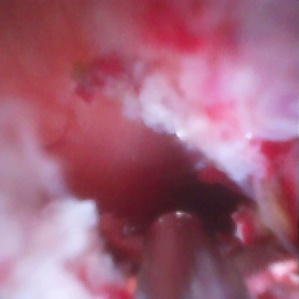

直视观察下胆管内新生物形成

术中,卢王主任使用十二指肠镜顺利插入十二指肠乳头,造影显示胆总管近十二指肠入口处狭窄,为进一步明确狭窄性质,进行了一次性使用电子胰胆管内窥镜直视下的胆道探查。在一次性胆道镜直视下可见胆总管下段新生物形成,表面凹凸不平,充血粗糙,局部狭窄形成,直视下精准活检成功明确诊断,并放置了胆道金属支架。整台手术仅耗时约30分钟,顺利完成。术后王奶奶黄疸逐渐减轻,食欲增加,恢复正常生活。